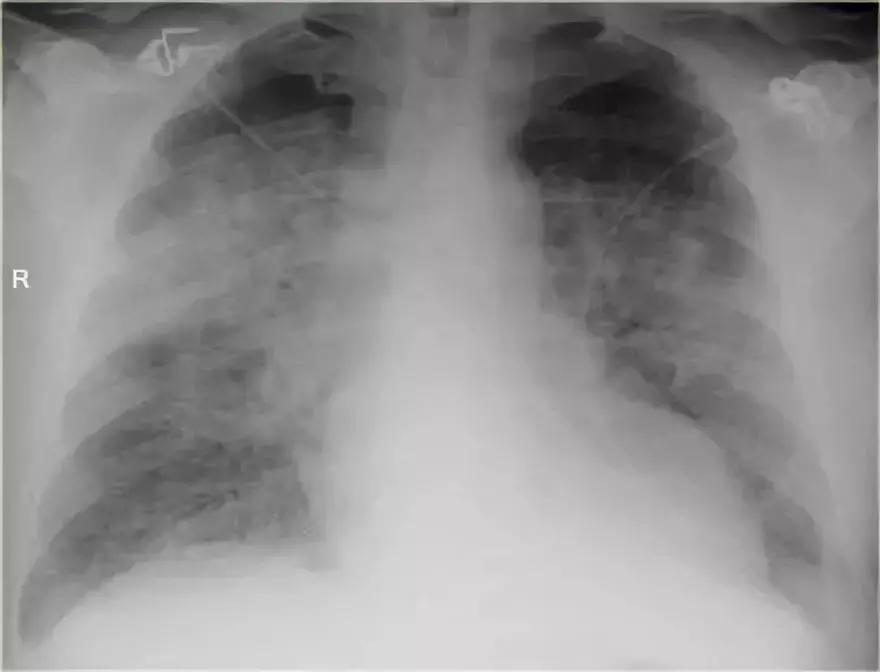

支气管肺炎弥漫性实变

➢ 患者患有高烧咳嗽,诊断为弥漫性支气管炎。

➢ 与始于肺泡的大叶性肺炎不同,支气管肺炎作为急性支气管炎始于气道。

➢ 多发模糊阴影,进展期能产生弥漫性实变,病变不能越过叶间裂,但通常在多个肺段发生。

➢ 支气管肺炎可由多种微生物引起

诊断结果:军团菌肺炎

图11 支气管肺炎弥漫性实变